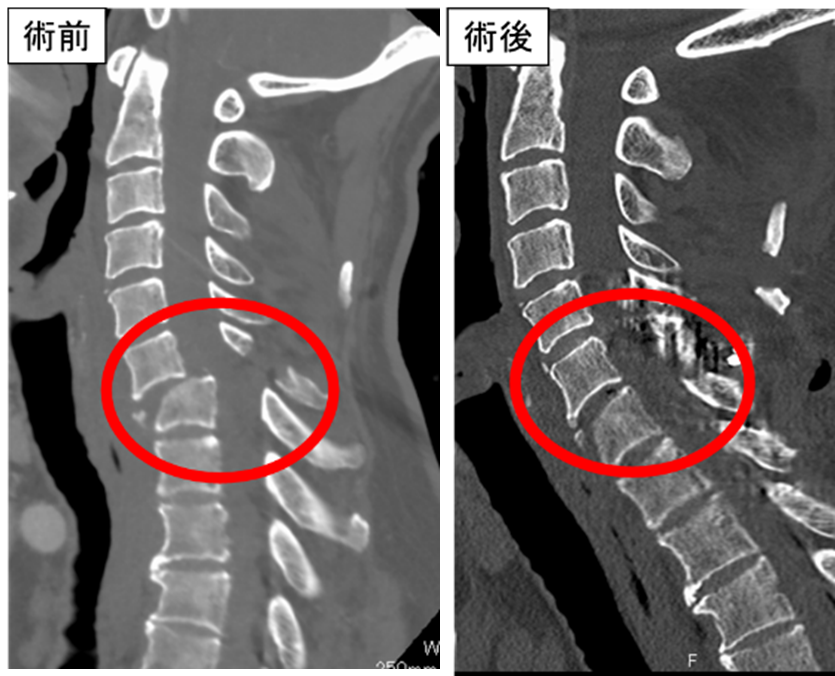

硬膜内髄外腫瘍による重度歩行障害に対し

術中脊髄モニタリングを用い腫瘍摘出術を行いました。

術後麻痺なく独歩可能です。

両下肢の脱力による歩行障害に対し脳外科医師

と協力し手術を行っています。術後しびれは残存

していますが、独歩可能です。